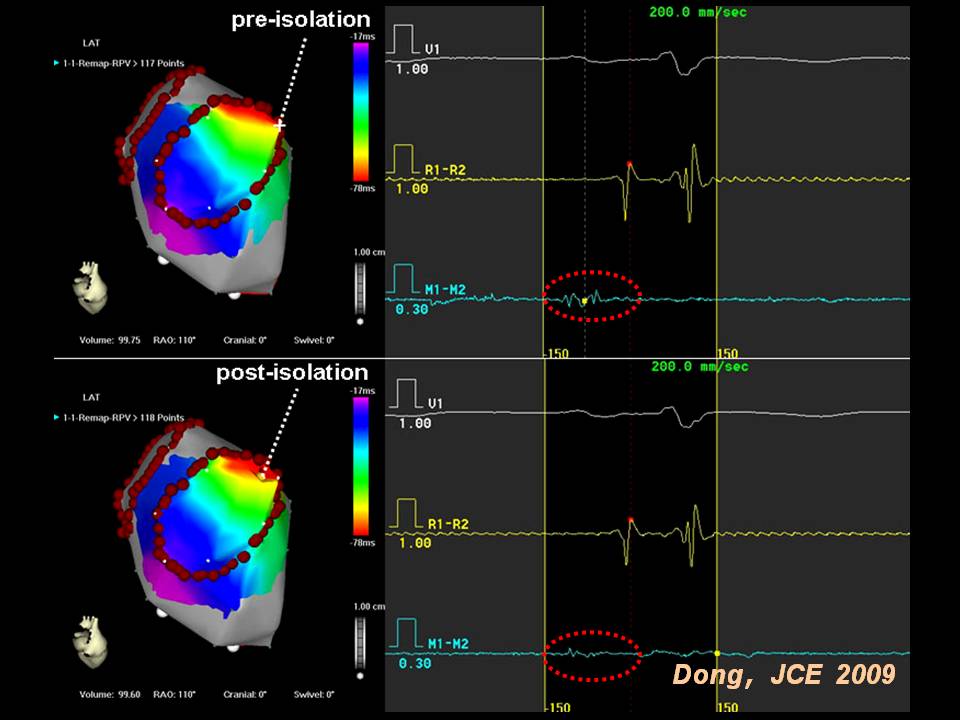

肺静脉隔离术难点

董建增